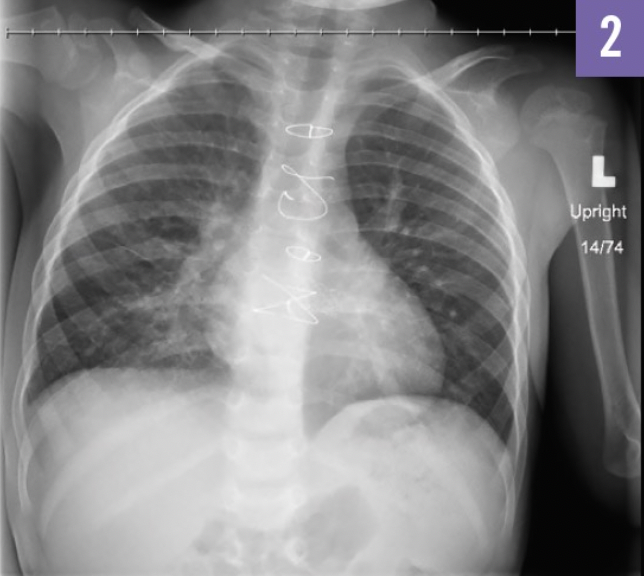

A follow-up chest radiograph after 4 months (Figure 2) was performed.

The follow-up chest radiograph (Figure 2) showed resolution of pneumonia. Repeated radiographic studies in the pediatric population with round pneumonia after appropriate antibiotic therapy have been shown to be of little value in patients whose clinical symptoms are responding well to treatment.